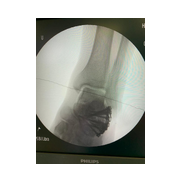

Görüntüleri büyütmek için resmin üstüne tıklayınız.